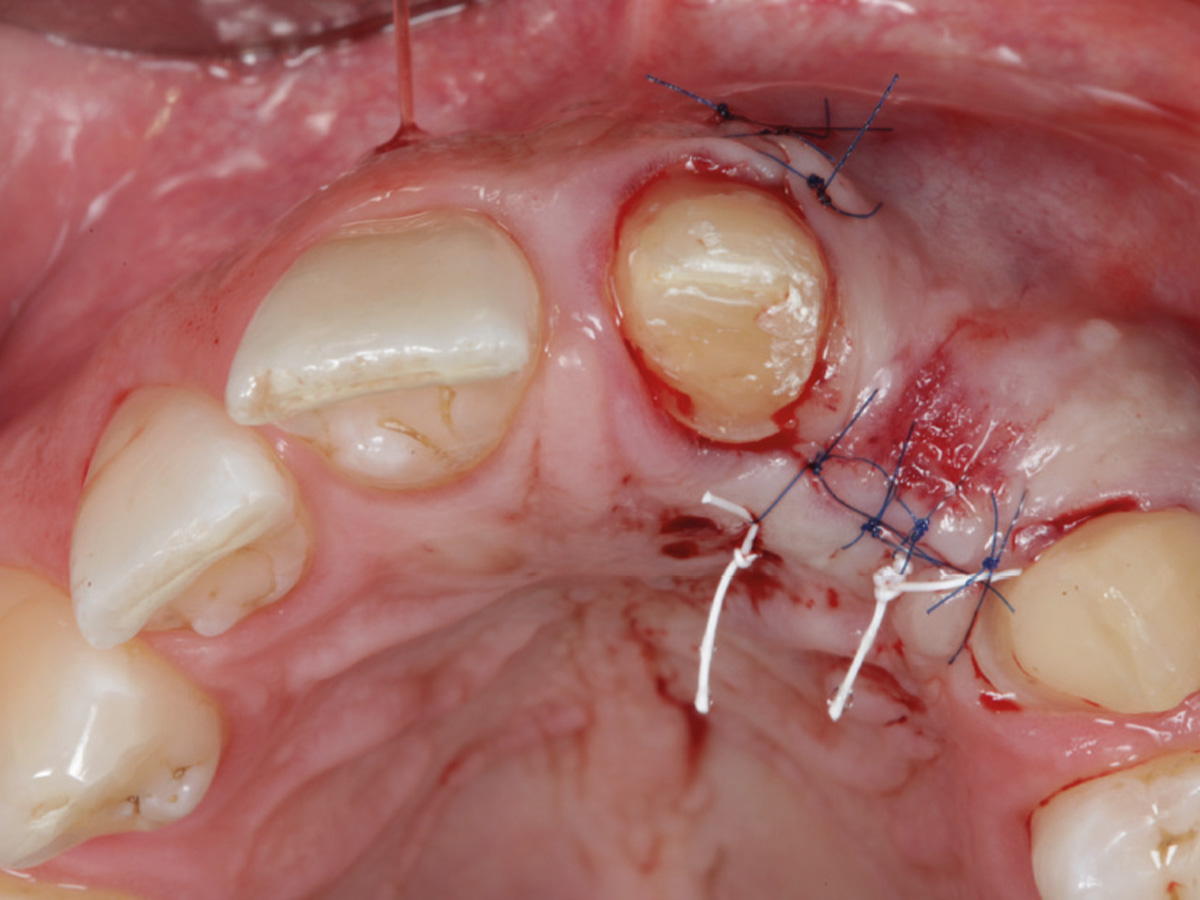

Abbildung 7

Der Weichgewebsverschluss muss spannungsfrei erfolgen. Einsatz von mikrochirurgischen Techniken.